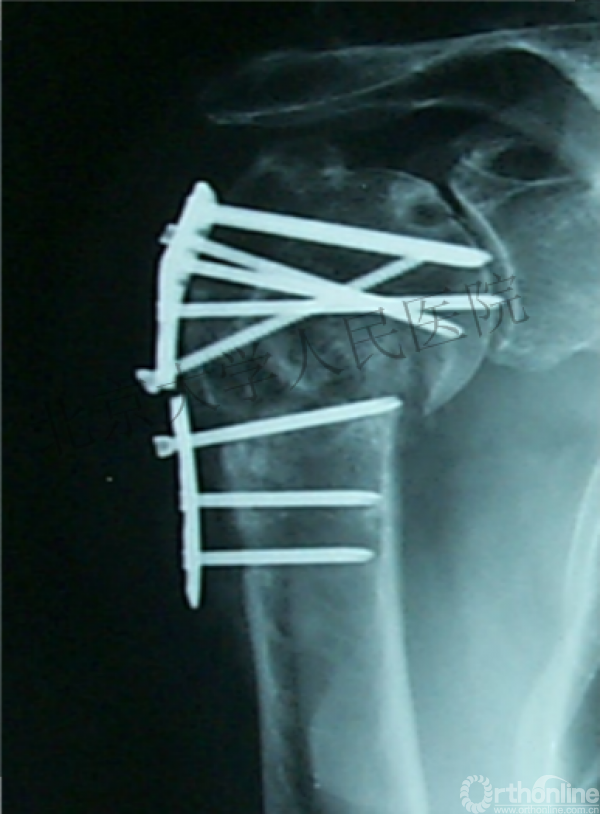

内侧皮质粉碎,低位外科颈骨折,肱骨头-干角维持困难。

术后复位丢失,肱骨头内翻畸形。

能否该偏心固定(钢板)为髓内固定,增加力臂?

早知今日,何必当初?

此时对比髓内钉是不是有很大优势?